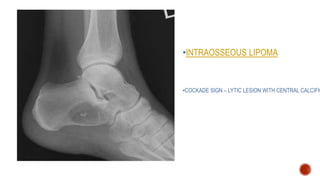

• I: INTRAOSSEOUS LIPOMA

•INTRAOSSEOUS LIPOMA

•COCKADE SIGN – LYTIC LESION WITH CENTRAL CALCIFIC